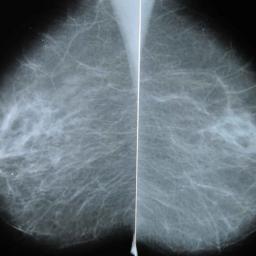

Many women with common breast cancer can skip chemo, study says

About 70% of women diagnosed with the early stages of one of the most common forms of breast cancer might not need chemotherapy as part of treatment, according to the results of a long-awaited study presented at the American Society of Clinical Oncology meeting in Chicago Sunday.